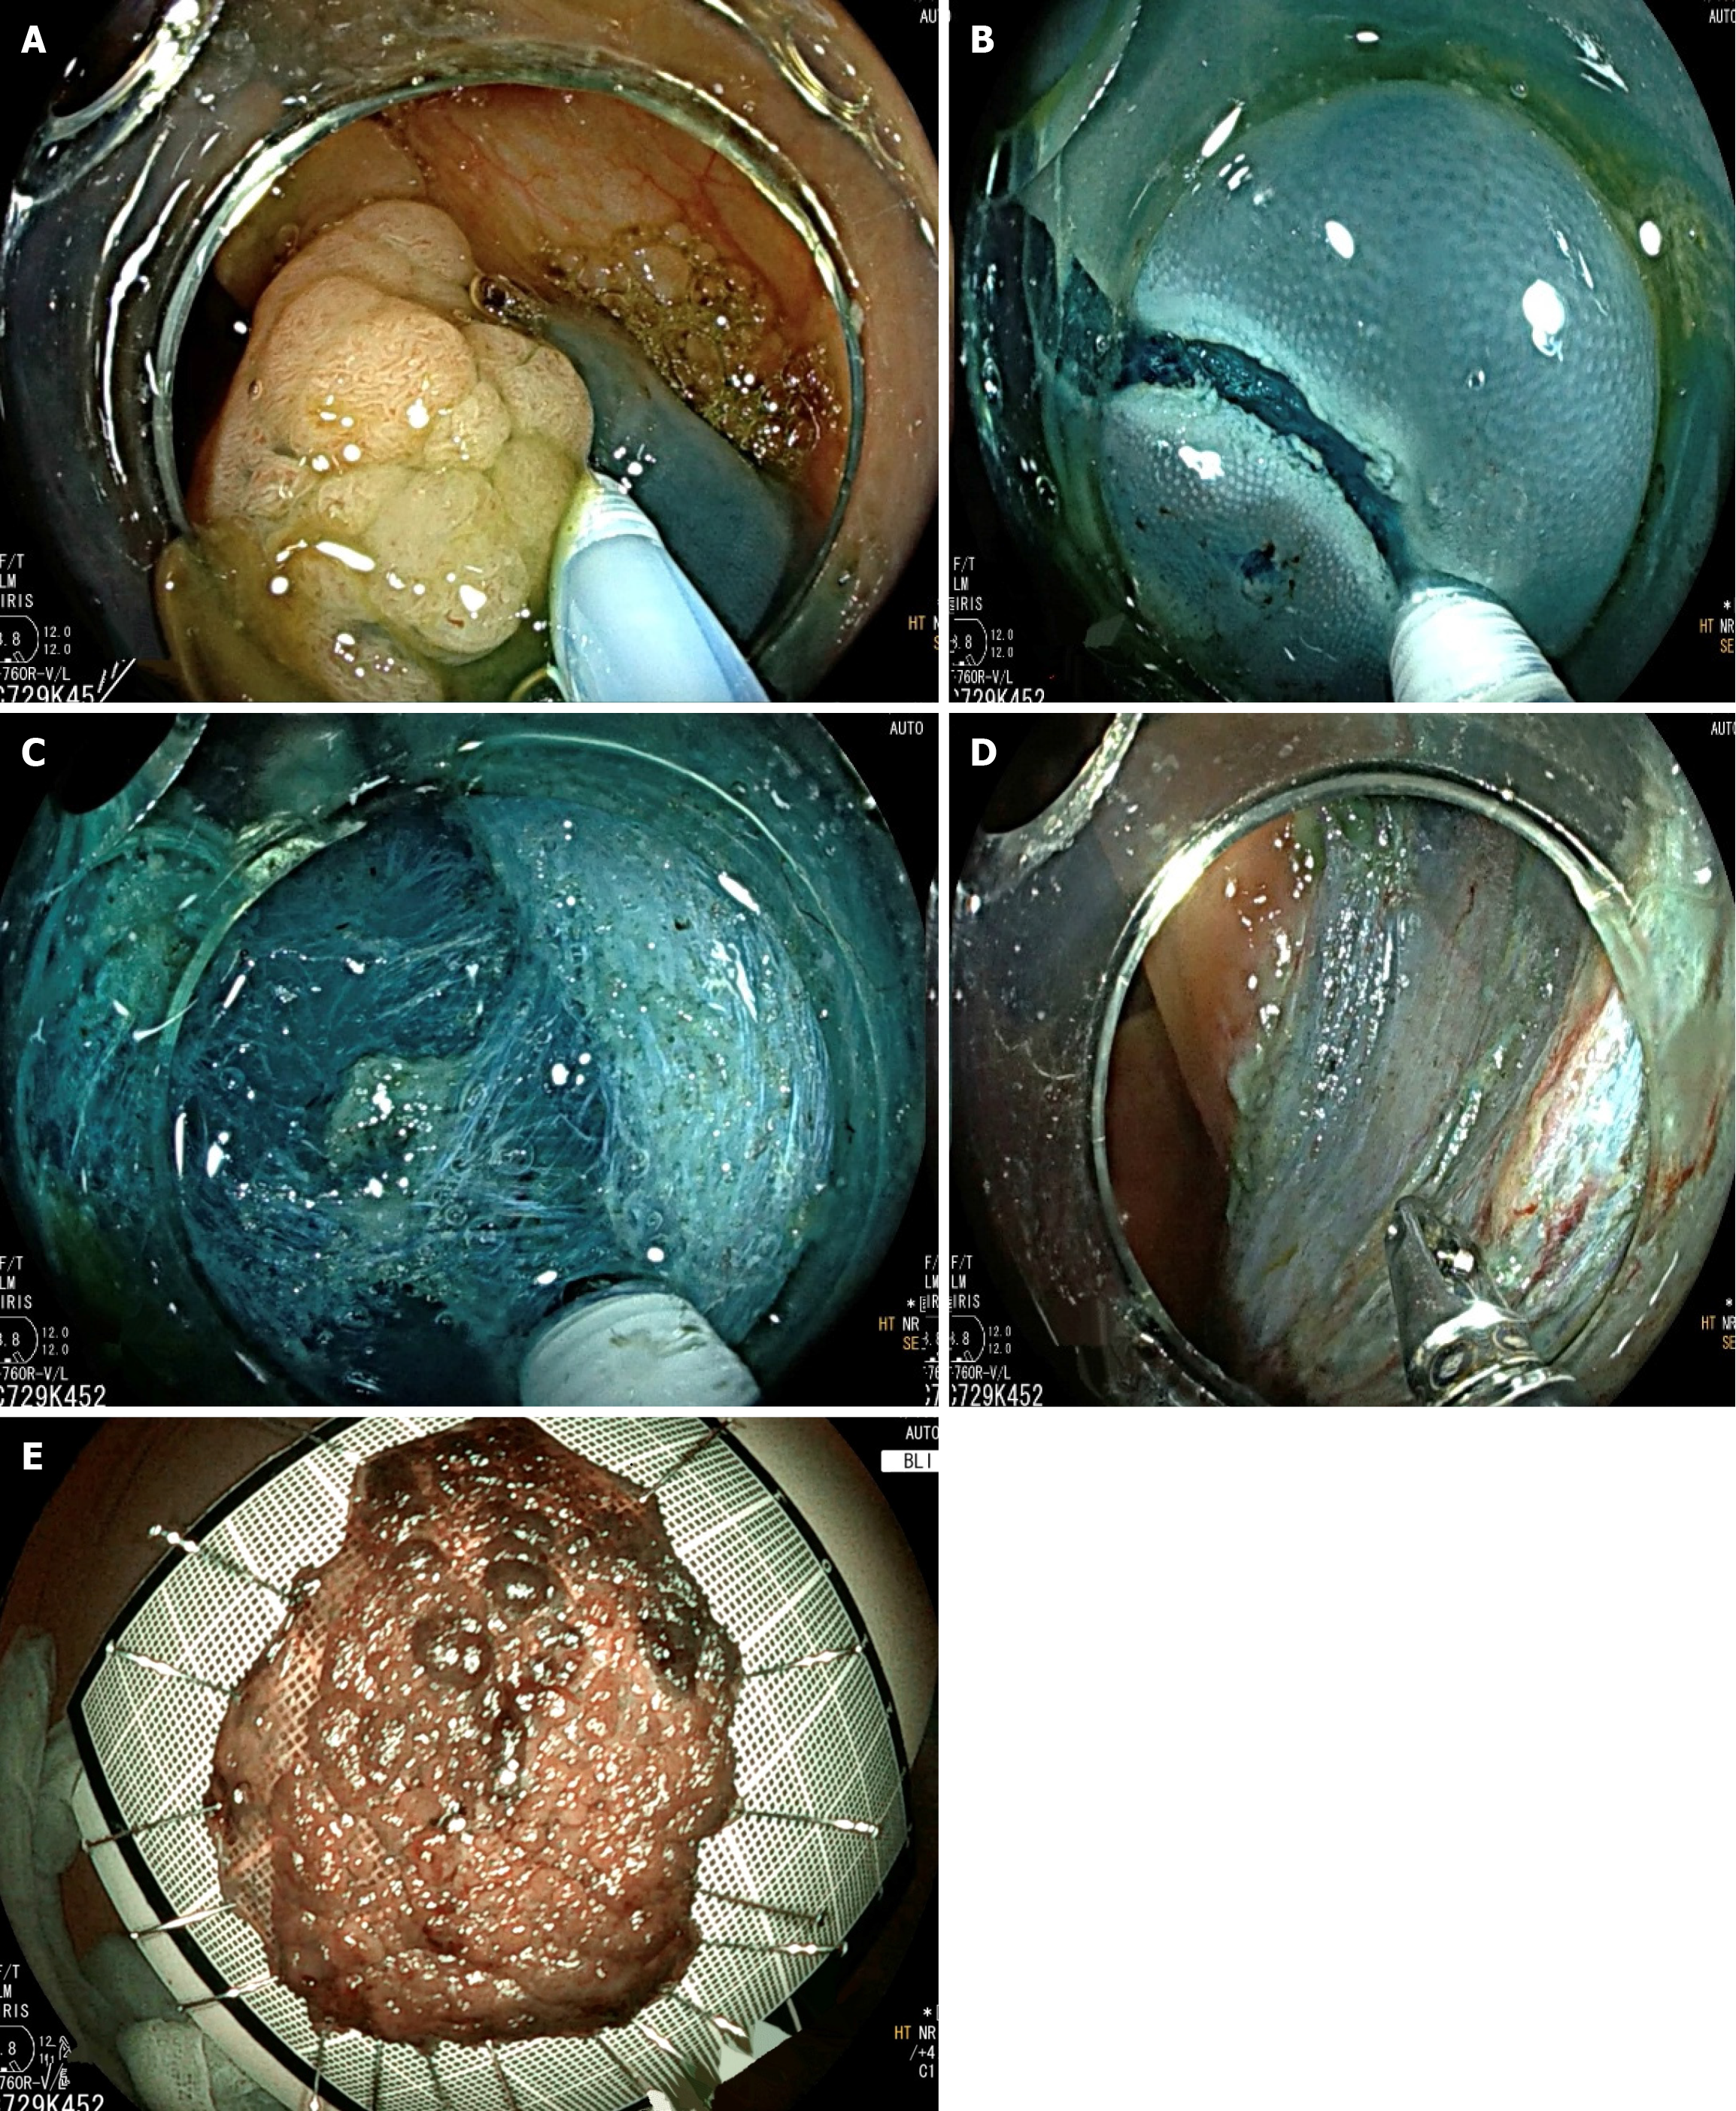

A novel resection method, called TEM-ESD, combines the least invasive ESD method with the technological benefits of rigid TEM tools (Figure 2). Low morbidity and local recurrence rates have been associated with the beneficial use of this technique in treating low-risk carcinomas and rectal adenomas[25]. The main characteristic of this technique is the use of traction through a separately operated grasper during the submucosal dissection. Its benefits are further demonstrated when resecting complex lesions, such as giant tumors and tumors in challenging locations.

Figure 2

Figure 2 Steps of transanal endoscopic microsurgery-assisted endoscopic submucosal dissection for a rectal lesion. A: Endoscopic view of the nodular lesion; B: Submucosal dissection is initiated (black arrow); C: Muscularis propria layer is preserved during dissection (black arrow); D: Post-dissection view showing the complete resection site with intact muscularis propria; E: Resected lesion pinned on a board for pathological assessment.